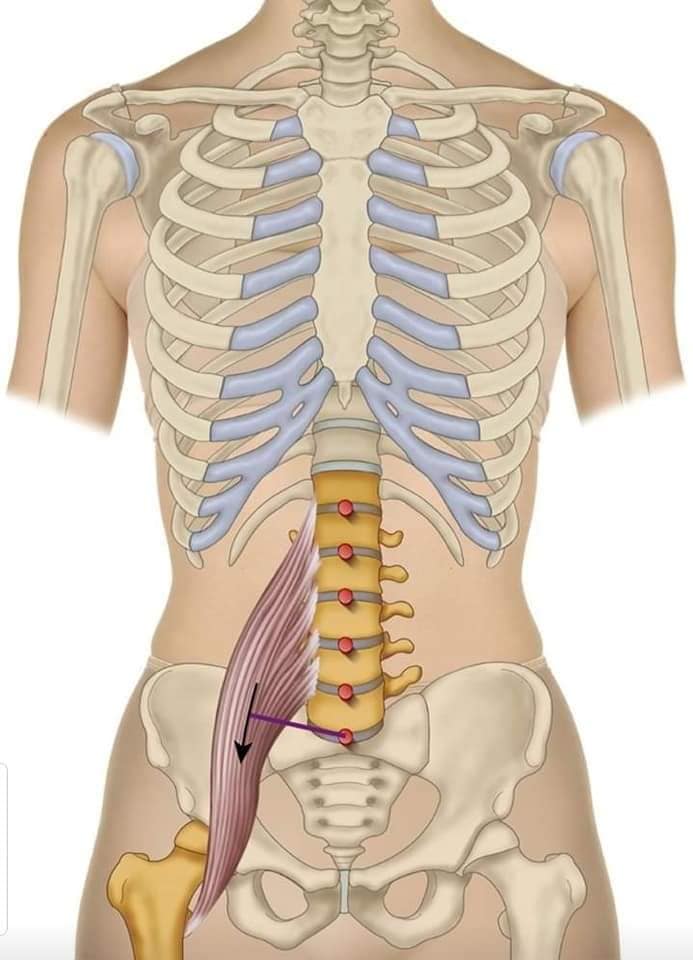

Спинні м'язи

Спинні м'язи виконують функції підтримки хребта, а також дозволяють здійснювати рухи тулуба.

Поверхневі спинні м'язи

М'язи, що піднімають лопатку: Трапецієподібний м'яз: великий м'яз, що покриває верхню частину спини. Його функція - підтримка і рух лопаток, а також забезпечення стабільності хребта.

М'язи, що ведуть лопатку до хребта: Широкий м'яз спини: великий м'яз, що розташований в нижній частині спини. Він відповідає за рухи плечей і лопаток, а також за розширення верхньої частини тулуба.

Глибинні спинні м'язи

М'язи, що забезпечують стабільність хребта: М'язи, що розташовані між хребцями: включають мускулатуру, яка забезпечує стабільність і підтримку хребта, а також дозволяє здійснювати рухи хребта.

М'язи, що здійснюють ротацію та нахили

М'язи, що забезпечують ротацію хребта: Ротаційні м'язи: допомагають у здійсненні обертальних рухів тулуба, а також у підтримці рівноваги і стабільності хребта.